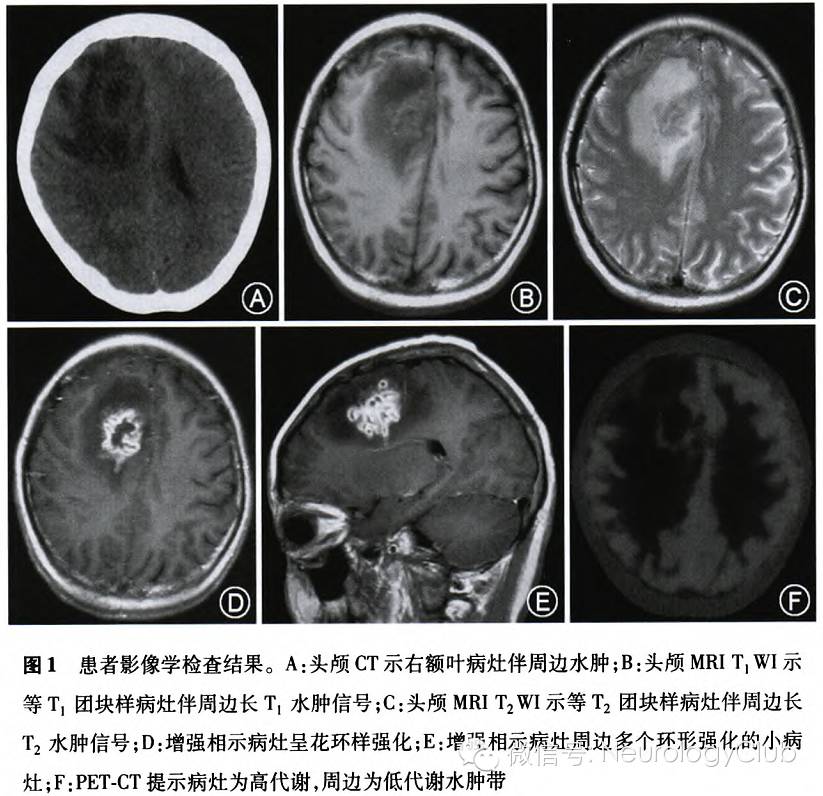

患者女性,28岁,主因“头痛伴恶心、呕吐20d,左侧肢体无力11d”于2012年9月收入我院。患者2008年无明显诱因出现皮肤多处色素沉着,于我院皮肤科门诊取皮肤病理示:表皮轻度增厚,局部单核细胞移入,真皮浅层血管周围轻中度淋巴、组织细胞浸润,诊断为“副银屑病”,“蕈样肉芽肿”不除外,予定期光疗,皮肤病变明显好转。2011年11月开始双侧腹股沟、右侧腋下多发淋巴结肿大,生长速度快,最大约鸡蛋大小,质硬,触之无疼痛,并出现局部皮肤色素沉着,至2012年2月逐渐出现颈部淋巴结肿大,皮肤病理示:表皮角化过度,少量异型淋巴细胞亲表皮现象,真皮血管周围少量淋巴细胞、组织细胞浸润,可见色素颗粒,考虑“蕈样肉芽肿”。皮肤科考虑“蕈样肉芽肿”累及淋巴结,遂开始进行干扰素300万U隔日1次治疗,患者淋巴结肿大无明显改善。2012年5月行颈部淋巴结活体组织检查,免疫组织化学检测示:细胞角蛋白AE1/AE3(-),CD1a(散在+),CD20(部分+),CD21(局灶+),CD3(弥漫+),S-100(散在+),平滑肌肌动蛋白(血管周围+),考虑非霍奇金淋巴瘤(外周T细胞性)。遂于我院血液科开始规律化学治疗(GDPML方案),具体方案为:吉西他滨1.5g(疗程第1天和第8天)+顺铂110mg(第1天)+地塞米松40mg(第1-4天)+甲氨蝶呤1.5g(第2天)+培门冬酶3750U(第8天)。2012年7月予第2疗程GDPML方案化学治疗,具体方案:吉西他滨1.5g(第1天)+顺铂110mg(第1天)+甲氨蝶呤1.5 g(第1天)+地塞米松40mg(第1-4天)+培门冬酶3750U(第5天)。行PET-CT提示全身多发淋巴结代谢增高,脾脏代谢增高。2012年9月1日患者在化学治疗过程中出现头痛,伴有恶心、呕吐,伴低热,体温37.5℃,当时未就医治疗。9月10日开始先后出现左下肢及左上肢无力,无言语不利、口角歪斜、肢体麻木等其他症状,就诊于我院急诊,行头颅CT检查示右额病灶伴周边水肿(图1A);头颅MRI增强+平扫示:右侧额叶大脑镰旁见一团块样异常信号,等T1、等T2为主,内见片状稍长T1、稍长T2信号,弥散加权成像为高信号,大小约3.0cm×4.1cm,灶周可见大片水肿信号,花环样增强;同时可见数个环形增强小病灶(图1B-E)。复查PET-CT示:原全身多发淋巴结代谢增高,脾脏新出现数个代谢增高灶,脑内新出现受累病灶(图1F);整体病程进展。急诊予甘露醇250ml 1次/8h脱水治疗,患者头痛稍好转,肢体无力继续加重,完全无法活动。为进一步诊治收入院。患者发病后精神、体力、睡眠较差,食欲可。大小便基本正常,自觉憋尿困难。体重较起病时减轻1kg。既往史、个人史、家族史:无特殊。未婚育。

北京大学第一医院神经科代表:患者为青年女性,亚急性起病,进行性加重病程,主要表现为头痛、恶心、呕吐伴有低热,后进展出现偏瘫,影像学提示右额叶占位性病变伴周边水肿,环形强化,PET高代谢;脑脊液检查未见明显炎性反应;既往诊断皮肤蕈样肉芽肿,外周T细胞淋巴瘤并接受化学治疗。定位诊断:左侧偏瘫定位于右侧皮质脊髓束;头痛恶心呕吐定位于脑脊液循环和脑膜系统;结合影像定位于右额叶。定性诊断:(1)中枢神经系统肿瘤,患者影像学所见病灶环形强化伴明显的周嗣水肿,且PET提示高代谢,均支持肿瘤性病变,从一元论角度首先考虑外周T细胞淋巴瘤累及颅内,但患者处于免疫抑制状态,颅内原发肿瘤如胶质瘤也需要考虑;(2)感染性疾病,如结核感染或其他机会性感染,患者免疫低下,需要考虑,但腰椎穿刺未见炎性反应为不支持点。鉴别诊断:进行性多灶性白质脑病,免疫抑制患者需考虑,但影像学表现不典型。

北京天坛医院神经科代表:患者青年女性,亚急性起病,有明确的淋巴瘤及化学治疗病史,存在免疫低下状态,头颅MRI提示病灶周边水肿及花环样强化,灶周可见数个小的环形增强病灶,诊断首先考虑颅内真菌感染,此病可慢性或亚急性起病,起病隐匿,临床表现无特异性,可出现脑膜炎、脑炎、硬膜下积脓、颅内肉芽肿或脓肿、真菌性动脉瘤、动脉炎等,常见致病菌包括感染免疫缺陷人群的念珠菌、曲霉和毛霉菌以及可感染健康人群的隐球菌、组织胞质菌、球孢子菌等,本患者以前一类病原体可能性大。此外还需要考虑寄生虫感染,如血吸虫、曼氏裂头蚴等,本患者缺乏相关流行病学资料和血清寄生虫抗体检查,尚无肯定证据。鉴别诊断:淋巴瘤颅内受累、HIV脑病、结核瘤、脱髓鞘性假瘤。

卫生部北京医院神经科代表:病史及定位诊断同前,定性诊断考虑脑弓形体病,患者有免疫缺陷病史,化学治疗过程中出现头痛、发热及局灶神经系统症状,首先考虑条件致病菌感染,而病灶以脑实质为主,脑膜反应轻,常见的有巨细胞病毒或弓形体感染。脑弓形体病病灶易累及灰白质交界或基底节,可多发,伴水肿及占位效应、环形强化,而巨细胞病毒易导致室管膜炎,强化病灶少见,故本例表现符合脑弓形体病。鉴别诊断:淋巴瘤颅内受累、隐球菌性肉芽肿。